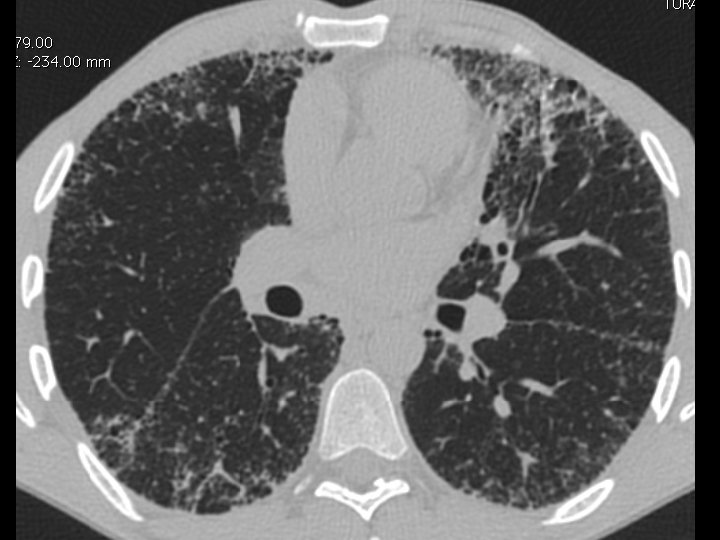

High-resolution CT scan

Subpleural, basal predominance Reticular abnormality Honeycombing with traction bronchiectasis UIPUIP Pattern

Subpleural, basal predominance Reticular abnormality Honeycombing with traction bronchiectasis Profuse micronodules UIPUIP Pattern Inconsistent with UIP Pattern

39 yo caucasian male, works in car collision repair and painting Multiple allergies, Gastroesophageal reflux disease and Thrombocytopenia of unknown etiology Smoker. No drugs CT: Reticular abnormality and honeycombing of subpleural basal predominance + micronodules Lung function tests: decreased diffusion capacity of the lung Blood tests: small increase of ESR and CRP; Autoimmune screening blood tests were normal BAL: normal celularity, with a mild increase in the neutrophil and eosinophil count

39 yo caucasian male, works in car collision repair and painting Multiple allergies, Gastroesophageal reflux disease and Thrombocytopenia of unknown etiology Smoker. No drugs CT: Reticular abnormality and honeycombing of subpleural basal predominance + micronodules Lung function tests: decreased diffusion capacity of the lung Blood tests: small increase of ESR and CRP; Autoimmune Screening Blood Tests were normal BAL: normal celularity, with a mild increase in the neutrophil and eosinophil count Definitive diagnosis can be established? Additional diagnostic tests required? Which tests?